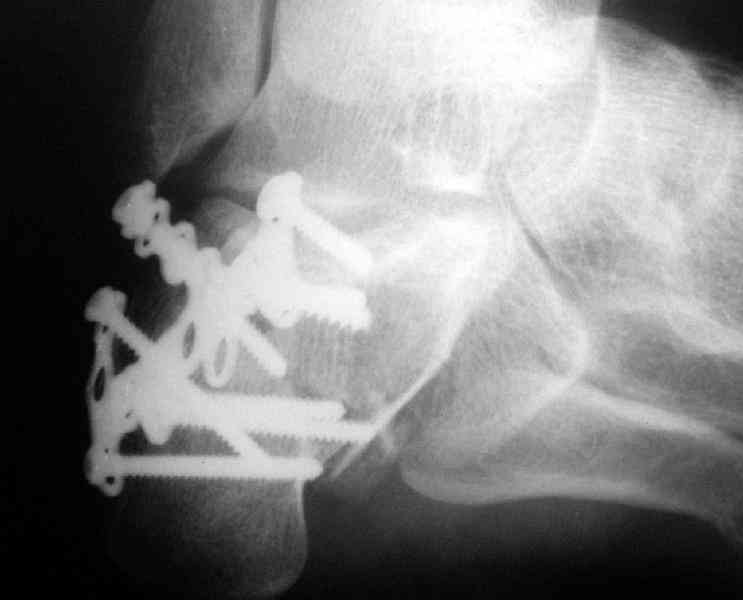

Пяточной пластиной

Открытый и закрытый способы лечения.

Its a comminuted one.

I myself would reduce it with EX-FIX and depending on the result would consider a plate on the table.

MOST OF MY COLLEGUES WOULD OPEN IT LATERALLY( a flap) and having a proper reduction would put a plate.

Имея какой-то опыт остесинтеза пяточной кости пластинами пришли к выводу - где есть альтернатива лучше без нее, где нет значит пластина и долгие переживания в ожидании очередной перевязки. Может нам так не везло, но и одного некроза( слава богу без остеомеилита) достаточно, чтобы призадуматься.